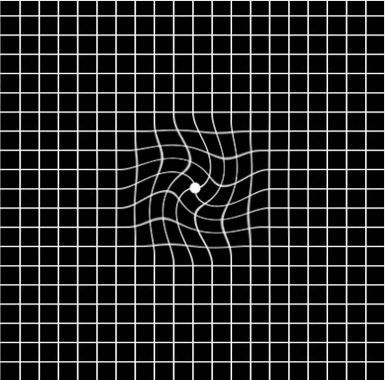

及早发现跟就诊对于治疗黄斑变性来说有很大作用,因此,如果发现自己出现中央视野缺损,或出现视力下降、视物扭曲、视物变色等黄斑变性的常见症状时,大家可以通过下面的阿姆斯勒方格表自测:

(视物变形、中心视野缺损)

(视物变形、中心视野缺损)

一旦出现上图视物变形、中心视野缺损等情况时,患者应及早到医院做进一步的详细检查,如果确诊,建议患者及时就医,以免对视力造成更严重的损伤。